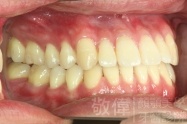

變臉矯正,原來戽斗妹跟大歪臉變成自信正妹

經由本院3D數影X光影像儀分析、與3D齒顎顏矯正技術,再配合口腔顎面正顎專科醫師施以正顎手術治療,雙方共同合作,使患者臉部外觀有很好的改善,大歪變小歪,產生了天南地北的大改變,她的人生也整個變得不一樣。

因為矯正與正顎手術的配合,使「戽斗妹」變成了「陽光正妹」,完全的改變了她的人生,在面對各種場合、與人交際都散發出自信微笑。所以,奉勸家長,如果小朋友有臉顎畸型的問題,應該考慮配合做這種簡單、安全、有效的正顎手術。